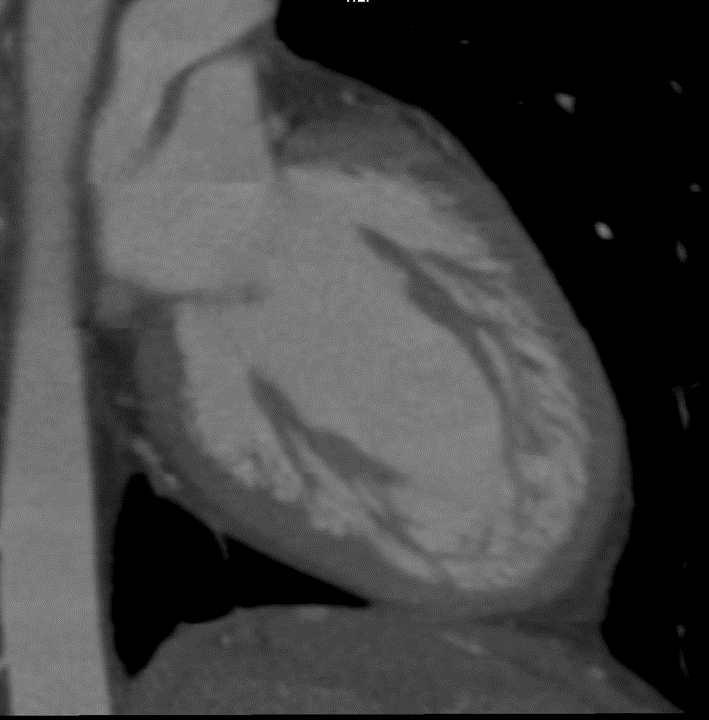

CT scan

Example showing increased trabeculations along the wall of the left ventricle.